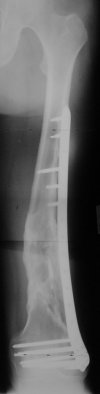

Attached are few examples from our Hospital:

A. Difficult reductions, even in retrograde nailing (my preference, easier control of "small" distal fragment) and it is much, much harder to do it anterograde (Alex, do you have one good case in your collection of anterograde nailing in very distal fractures - as you have suggested that I

should have done it in my previously posted case?

Malpositioning is much too common (recurvatum, varus - valgus).

B. Fixation loosening: distal cutting of the nail, non-unions do happen (cases attached).

Locking Plating has more distal screws than any nail, fixed angles and provides much better fixation, especially in osteoporotic bone.